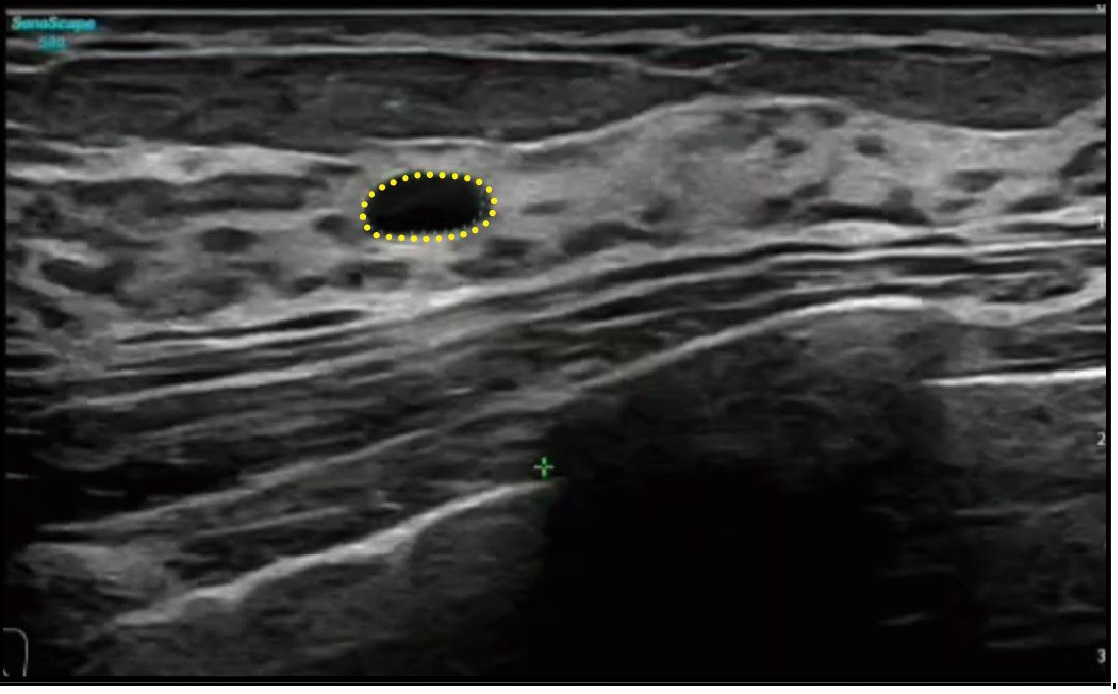

S Tyroid

S-Thyroid, ACR TI-RADS kılavuzlarına dayanarak şüpheli tiroid lezyonlarını tespit eden ve sınıflandıran gelişmiş bir araçtır. Bu sistem, lezyon sınırlarını otomatik olarak belirler ve ardından otomatik bir rapor oluşturur.